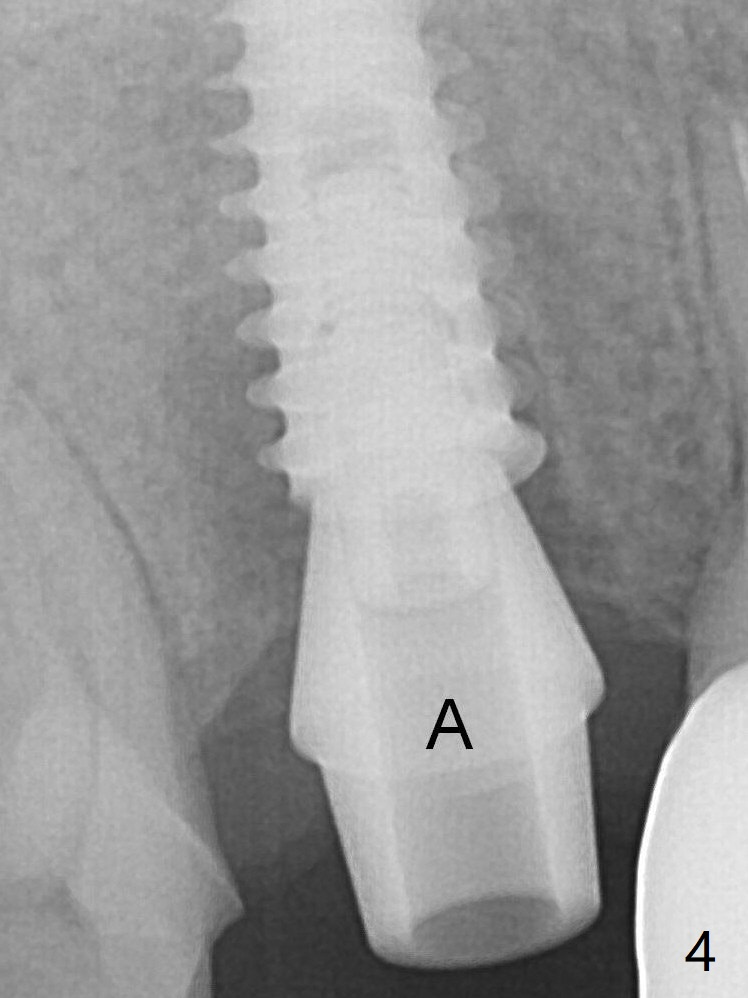

To reduce the gap and periimplantitis, a 5x11 mm IBS implant is placed with insertion torque > 50 Ncm after further osteotomy using Magic Drills (Fig.4). Following placement of 5.5x4(4) mm abutment (A), a splinted provisional is fabricated at #3 and 4. The provisional is stable 3 months postop (Fig.7). Bone graft appears to remain between the implant fins (arrows). The bone density of the bone graft between the implant fins increases 4.5 months postop (Fig.9).